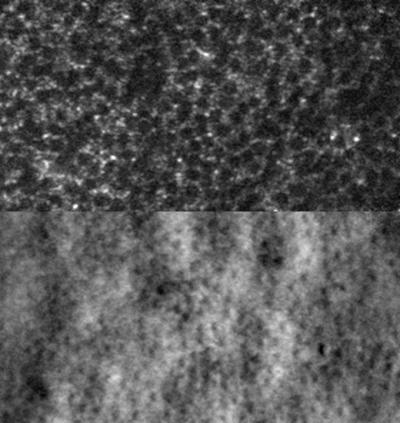

Widespread dark cones identified in a patient with oligocone trichromacy

Widespread dark cones identified in a patient with oligocone trichromacy. Confocal reflectance image (top) showing dark cones surrounded by reflective rods and non-confocal split detection image (bottom) showing the presence of cone photoreceptors at locations where dark cones are observed.

Read the associated publication